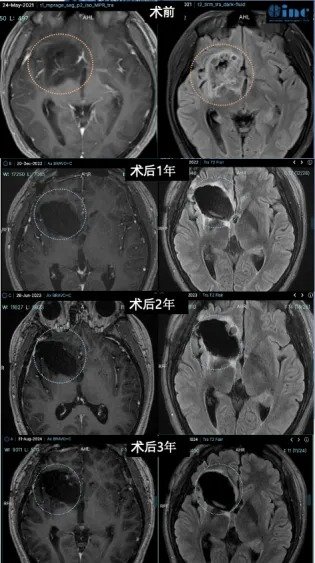

▼术前术后影像资料:

术后情况:手术1年多后,复查核磁显示肿瘤的切除效果非常理想,局部血管及其他重要结构均得到完整保留。巴教授也为小欧如今的状态感到高兴。如今,小欧的癫痫发作频率明显减少,在随访时,他还可以用流利的英语与巴教授对话,像一个“小大人”般描述自己目前的身体状况,聪明又懂事,令一旁的父母深感欣慰。